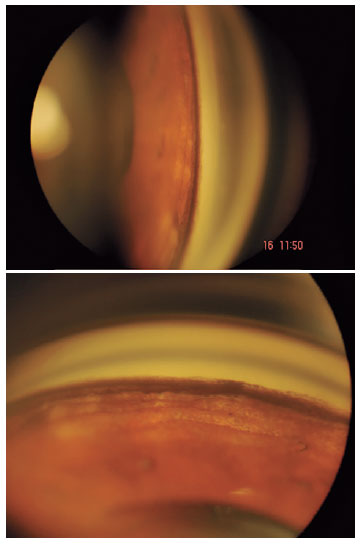

A 62-year-old woman was first evaluated in April 2019 with acute onset of bilateral eye pain and photophobia. Visual acuity was 20/20 in both eyes. Examination revealed bilateral involvement with ciliary injection, circulating pigment in the AC, patchy areas of iris depigmentation, posterior synechiae, and ocular hypertension (34 mmHg). Pupils were distorted, sluggish, and slightly dilated, but there were no iris transillumination defects (Figure 1). There were also no inflammatory keratic precipitates. The vitreous was clear, and the fundus and optic discs were normal (C/D ratio 0.4/0.5). She had a history of pneumonia and sinusitis two months earlier, which had been treated with oral amoxicillin-clavulanate and moxifloxacin.

02-fig01.jpg)